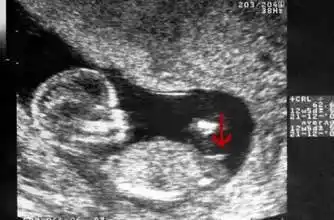

怀孕13周后的一次重要产检结果超过这个数值要当心胎儿畸形了

一口气教您读懂超声nt报告_胎儿_筛查_检查